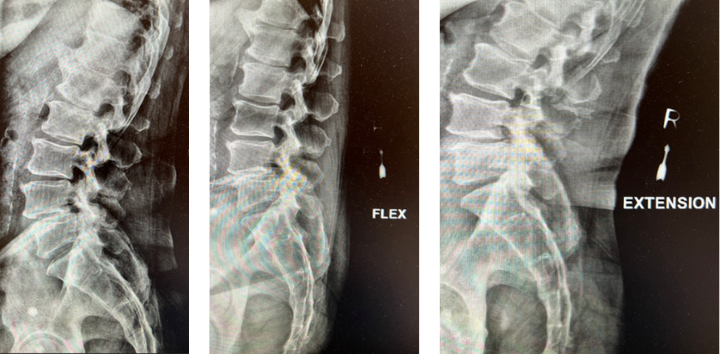

The grade 1 spondylolisthesis at L4/L5 requires both decompression at the L4/L5 level but also fusion because of the instability with motions. Here are three standing x-rays: one in the neutral position, one in flexion, and one in extensions. Notice the movement in the vertebral bodies at L4 and L5. This is abnormal motion and it can contribute to back pain and increase stenosis in certain positions. Thus, it requires decompression and stabilization with fusions.

Image 2. This shows the lumbar spine in motion. Notice the L4 and L5 level changes with flexion and extension. Notice the L2 and L3 levels do not have that type of motion. This is instability.

The herniated disc only requires decompression and removal of the herniated disc. Notice in the same flexion extension dynamic x-rays. There’s no abnormal motion at the L2/L3 level.